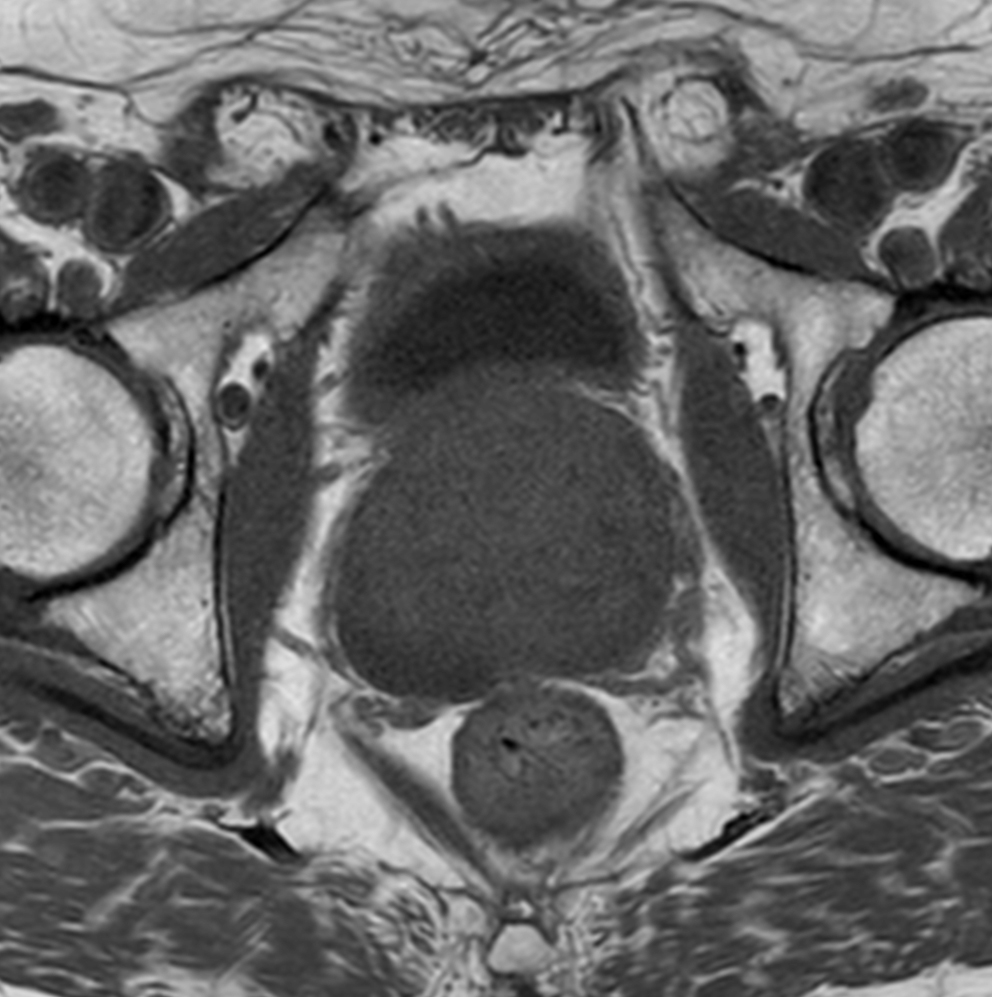

Axial T2w TSE - MultiVane XD